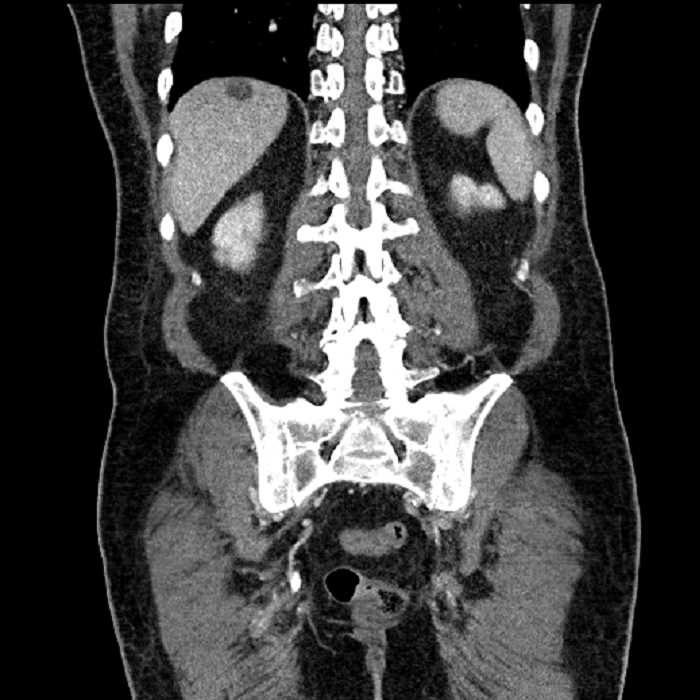

• High grade stenosis of the left common iliac artery, with the left internal and external iliac arteries remaining patent

• Ankylosis of both sacroiliac joints

High grade stenosis of the left common iliac artery. The left external and internal iliac arteries are patent.